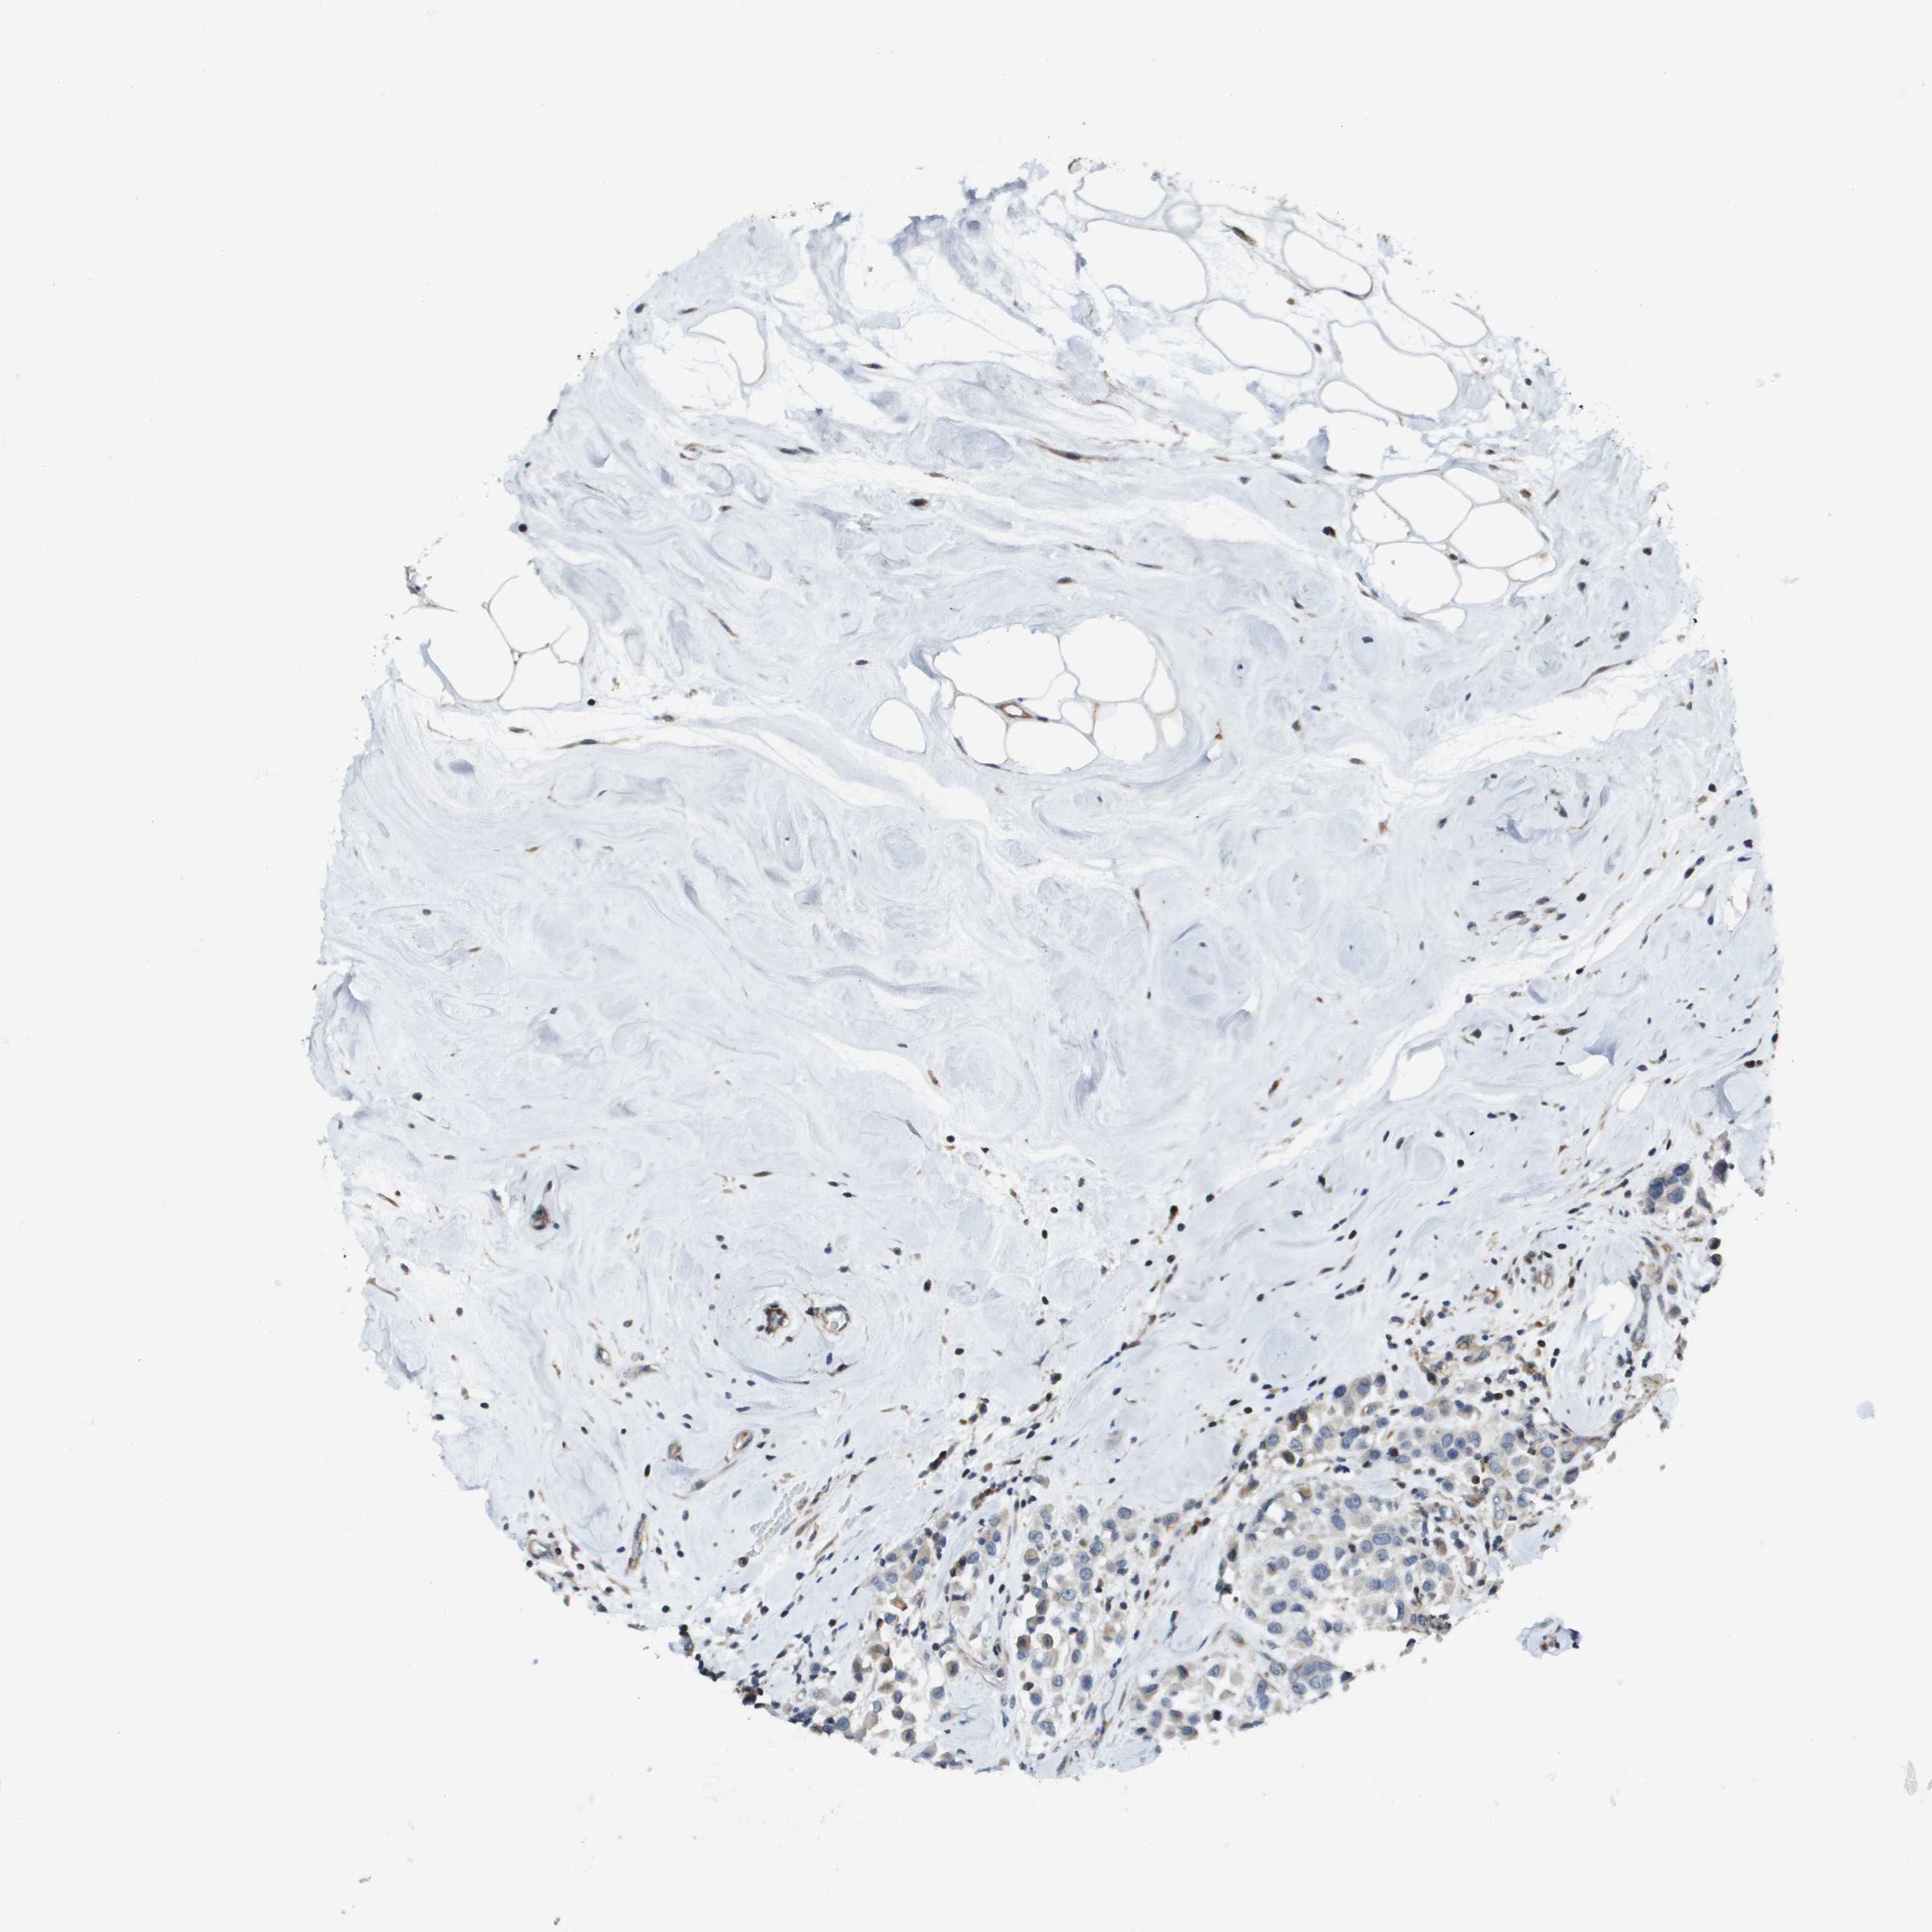

BRCA TCGA BRCA VALIDATION PROTEIN EXPRESSION

ANTIBODIES

AND

VALIDATION